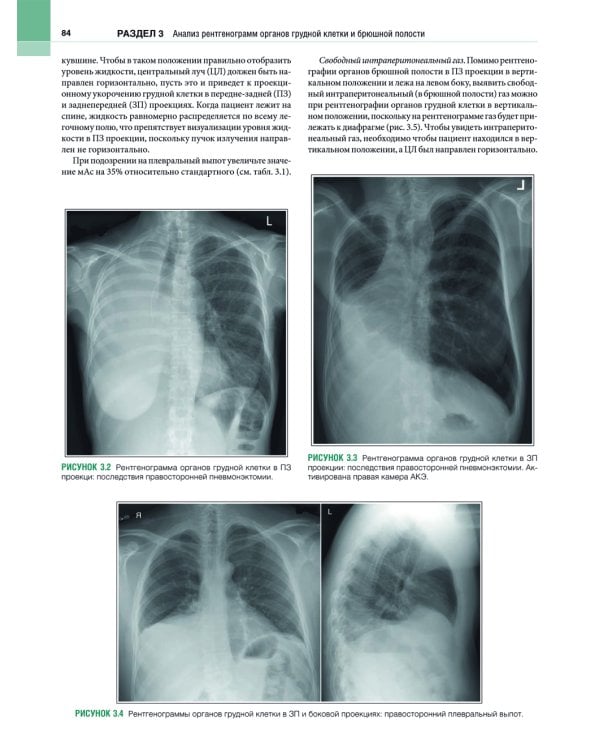

В этом практическом руководстве описаны основные методики выполнения рентгенографии и принципы анализа качества рентгенограмм, стандартные технические параметры исследования, а также варианты укладки и способы их коррекции. Особое внимание уделено базовым принципам получения и цифровой обработки изображений. Для каждой рентгенологической методики приведены фотографии правильной укладки пациента, варианты укладки в нестандартных ситуациях и при определенных патологических состояниях, а также таблицы с сопоставлением вариантов укладки, примеры определения центрального луча или приемника изображения, рисунки и фотографии костных препаратов и условного пациента, позволяющие точнее отобразить взаимное расположение анатомических структур, если проекционное искажение затрудняет интерпретацию рентгенограмм. Издание содержит более 1500 иллюстраций. Книга предназначена для рентгенологов.| Издательство | ИЗД.ПАНФИЛОВА |